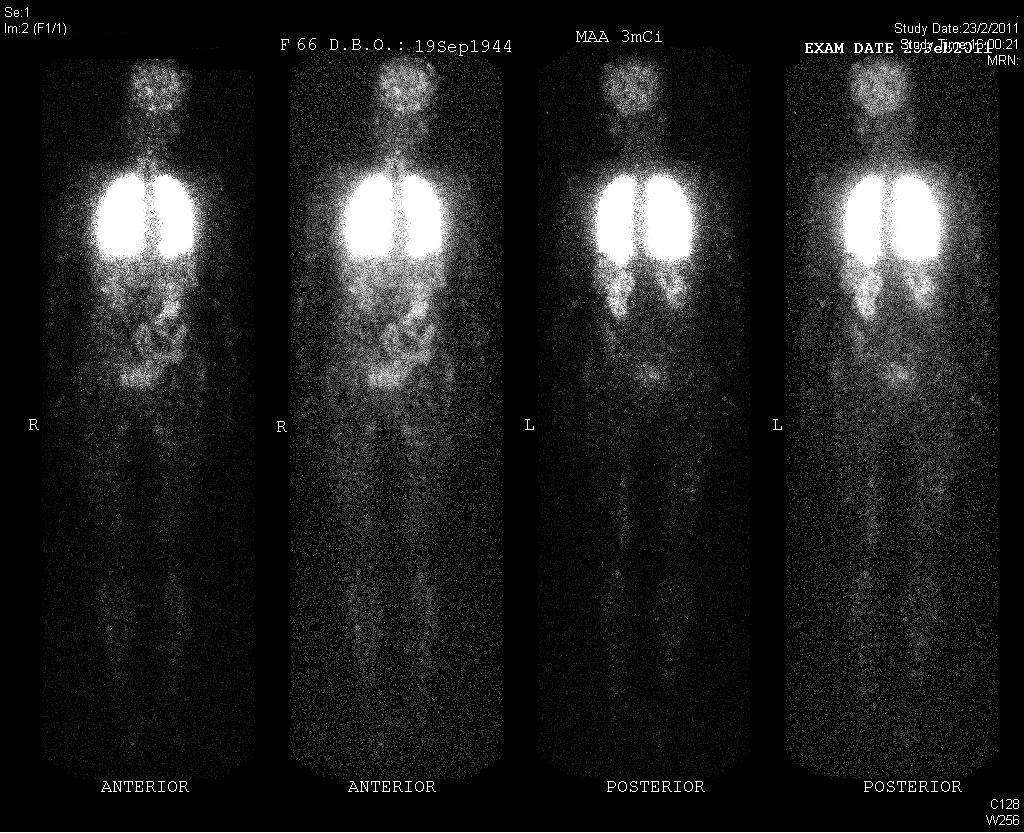

High resolution computer tomography (HRCT) scan of the thorax that time had no evidence of interstitial lung disease. Physical examination on admission revealed multiple telangiectasia over her forehead. Lung auscultations had no added sounds. Chest X-ray had no definite consolidative changes over lung fields. However, she was found to have persistent desaturation despite given high flow oxygen via non-rebreathing mask. White cell count was normal. Augmentin was empirically started. Arterial blood gas (ABG) showed type 1 respiratory failure with increased A-a gradient. She was eventually given Bi-level Positive Airway Pressure (BIPAP) support and intubated on day 2. Urgent contrast computer tomography scan of the thorax was performed, which incidentally found multiple PAVMs over bilateral lower zones of her lungs. There were no evidence of pulmonary embolism and no significant consolidative changes over both lungs. She was then transferred intensive care unit for further management and was successfully weaned from mechanial ventilation. Significant intra-pulmonary shunt was confirmed by contrast echocardiography. However, despite stabilization, she had persistent hypoxemia requiring oxygen supplement of 4L/min on discharge from acute medical ward. Detailed history confirmed that she had personal history of epistaxis since 25 year old. She was therefore diagnosed to have hereditary hemorrhagic telangiectasia by Cucao Criteria. Radionuclide scan by 99m Tc was arranged and shunt fraction was estimated to be 24.6% after calculation. Lung function test showed isolated decreased DLCO of 58% predicted after adjusted with alveolar volume.

To diagnose PAVM, several methods can be used to demonstrate intra-pulmonary shunt2. 100% oxygen method, which requires measuring partial pressure of alveolar oxygen (PaO2) and arterial oxygen saturation (SaO2) after breathing with 100% oxygen for 20 minutes, is sensitive but the accuracy is operator-dependent. Shunt fraction is then calculated by equations. Further investigations are recommended if shunt fraction is more than 5%. Contrast echocardiography is the next option. By injecting agitated saline into a peripheral vein of the patient, echocardiogram is performed to demonstrate any abnormal bubbles in the left heart chambers so as to confirm presence and severity of shunting. Contrast echocardiography is again very sensitive to diagnose shunt but alone is difficult to quantify shunt fraction. Therefore, a scoring system (from Grade 0-4) is advocated in the literature3. Though not universally recognized, study showed that it had good correlation with radiological detection of PAVM by computer tomography and even size of the feeding artery. Radionuclide imaging by technetium-99m (99m Tc) is another alternative method to diagnose PAVM but it is expensive and not widely available. It is less operator dependent than 100% oxygen method. Shunt fraction can be calculated by Gates’ semi-quantitative equation.

Figure 2: Tc-99m lung perfusion scan showed abnormal uptakes in brain, thyroid, kidneys and bowel